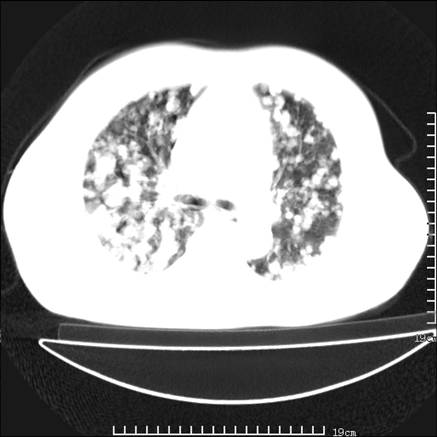

张男,75岁,干咳半年余,小便不利二年,b超检查前列腺增大,未见明显肿块;前列腺癌血生化检查多项指标明显增高。

双肺内多发转移瘤,纵膈淋巴结转移。来源前列腺?建议盆腔mri进一步检查。

双肺转移满了。

两肺广泛转移瘤。